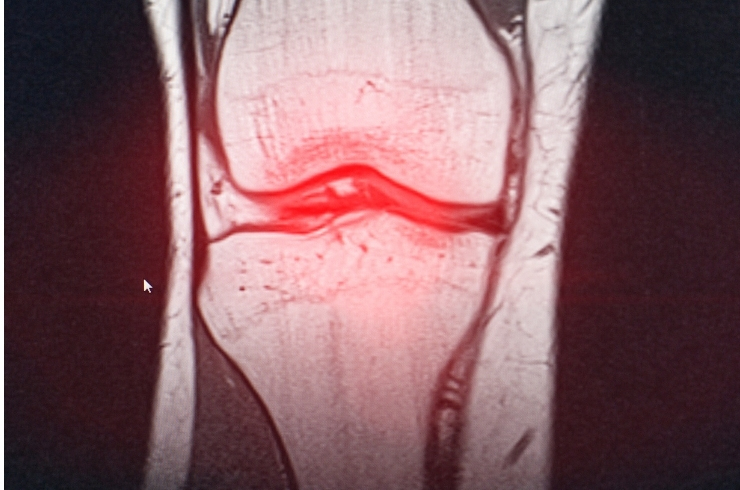

Minimally invasive knee procedures to repair ligaments, restore stability, reduce pain, and enable faster functional recovery.

Advanced techniques to repair meniscus and preserve cartilage, preventing degeneration and maintaining long-term joint health.

Advanced corrective procedures to realign knee joints, reduce pain, delay replacement surgery, and improve long-term joint function effectively and safely for patients.

Innovative procedures to repair damaged cartilage, restore joint surfaces, and improve movement while delaying joint replacement.